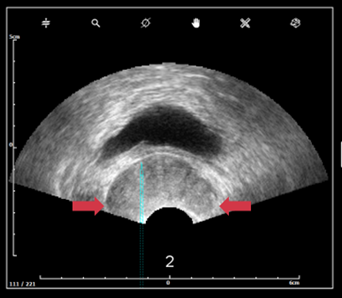

d. Pression sur la sonde et image

- Les lobes dépassent l’image (image de gauche (6)) → déformation de la glande due à une pression excessive sur la prostate).

- La prostate est trop loin de la tête de sonde (image de droite (14)) → pas assez de pression).

- Les lignes blanches de la tête de sonde doivent être continues.

- Les images ultrasons ne doivent pas avoir de lignes noires continues(bruit ultrasons).